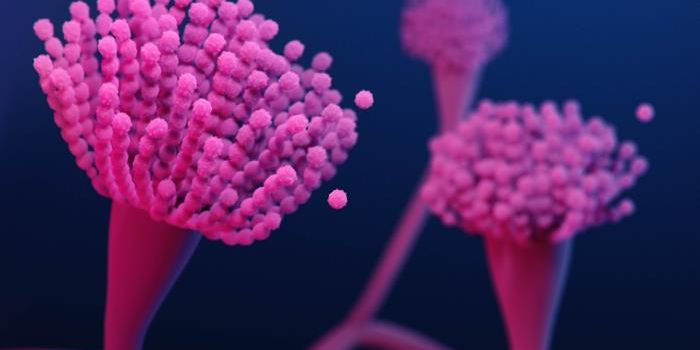

AUG 20, 2024MicrobiologyFungi are everywhere, and in many cases, a fungal infection can be eliminated by a person's immune system. But fungal in ...

JUN 30, 2024Earth & The EnvironmentAspergillus is a common fungus that produces spores, which can be found in many indoor and outdoor environments. There a ...

JUN 23, 2024Earth & The EnvironmentWe're nowhere near a world like the one in HBO's The Last of Us, but there have been notable increases in fungal infecti ...